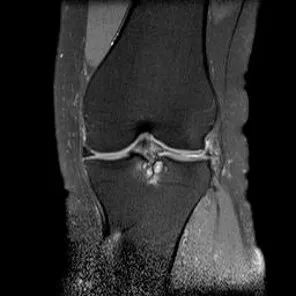

半月板桶柄状撕裂

1、多为纵形撕裂的特殊形式,有时来源于垂直(纵行)和水平撕裂2、多见于严重外伤的年轻患者3、内侧半月板发生率是外侧半月板的3倍

桶柄状撕裂MRI表现

1、宽度减小,在通过半月板体部的冠状面上蝶形消失,同时可见内移的半月板位于髁间窝、交叉韧带旁2、矢状面示残余的前角或后角变小或截断3、半月板前(后)角增宽或双半月板前(后)角征4、双前交叉韧带或双后交叉韧带征

桶柄状撕裂:宽度减小,在通过半月板体部的冠状面上蝶形消失,同时可见内移的半月板位于髁间窝、交叉韧带旁